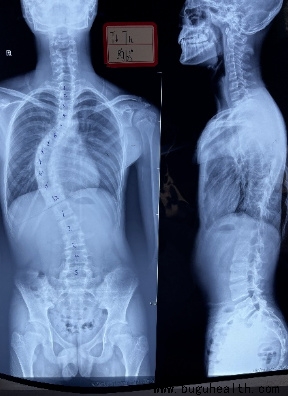

例子一:这是一个12岁的孩子,平时住校,当我们看到第一张图的时候好像没有什么问题,当脱去外套的时候,只是发现两边肩膀不一样高,好像也没有什么大问题,但是当她弯腰的时候就很明显看出脊柱两边的肌肉不一样高,就是剃刀背已经很明显了,最后我们再来看看拍出来的片子,孩子的侧弯已经很大了。那她是怎么发现的呢,孩子平时一点感觉都没有,全身不痒不痛,有一天洗澡的时候被同学发现背部两边差别很大,才让父母带来看,才发现是脊柱侧弯。

例子二:这是一个14岁的男孩,也是住校,父母常年在外务工,当父母过年回家发现孩子背部不对劲的时候,来检查侧弯已经很大很大了,孩子侧弯度数这么大也是不痒不痛,但是这个70多度的侧弯只能做手术了。